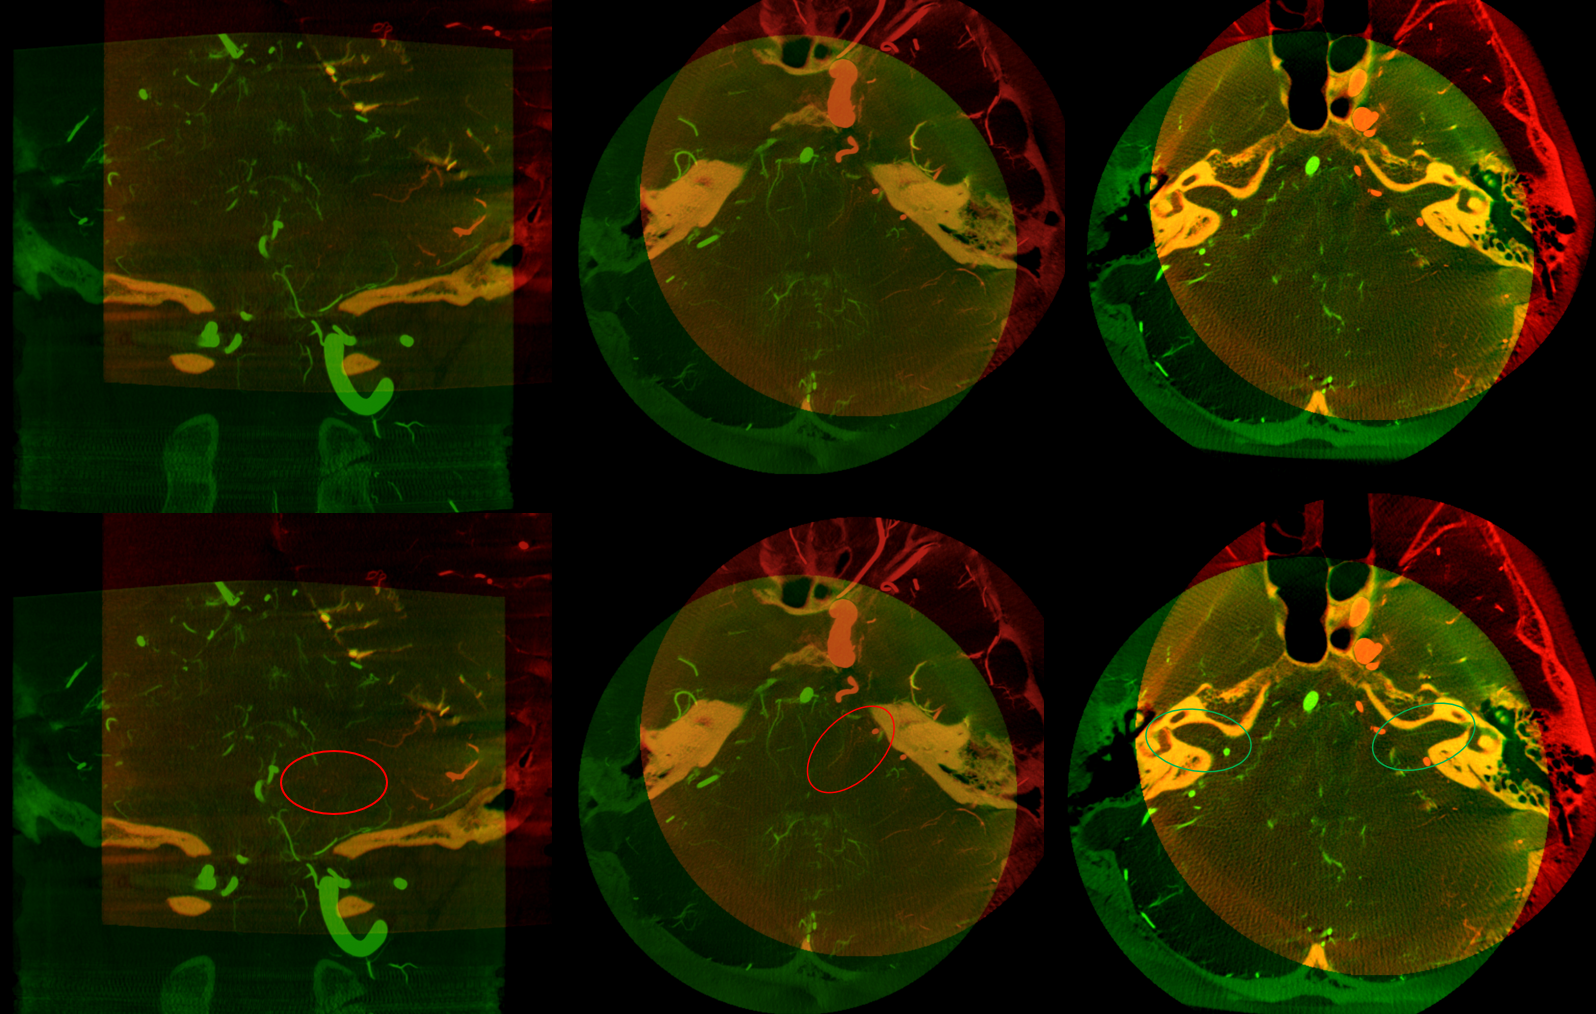

Angio shows large trigeminal with clear supply of the SCA on lateral view. Vert injection shows no right SCA. There is a diminutive branch from mid-basilar projecting laterally — that is likely the right labyrinthine artery — what is embryologically solid AICA territory. The rest is taken by the trigeminal. The right PICA is limited to vermian territory. The inferolateral hemisphere is supplied by the trigeminal as well. Dont look for arrows. You should figure it out.

DYNA VR. White arrow — vermian branch SCA; dashed white arrows — lateral hemispheric branches of SCA; red arrow — AICA. Note inferior extension towards PICA territory.

MIP images. Superior vermian territory = white oval; lateral SCA territory = dashed white oval; AICA (minus the labyrinthine branch) = dashed black oval; inferior PICA/down to tonsillar branch = black oval